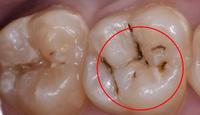

窝沟黑线图片

牙齿吃东西的时候酸痛,牙窝有黑线,严重吗?

牙沟上黑线,需要补牙吗?

窝沟出现了黑线,刷牙刷不掉怎么办?

口腔疾病 | 牙齿上刷不掉的黑线,究竟是啥?

牙齿上有黑线,就一定是蛀牙吗?_治疗_口腔_附院

窝沟发黑需要补吗?

但是有一种龋齿也会让后牙槽出现黑线—— 那就是窝沟龋